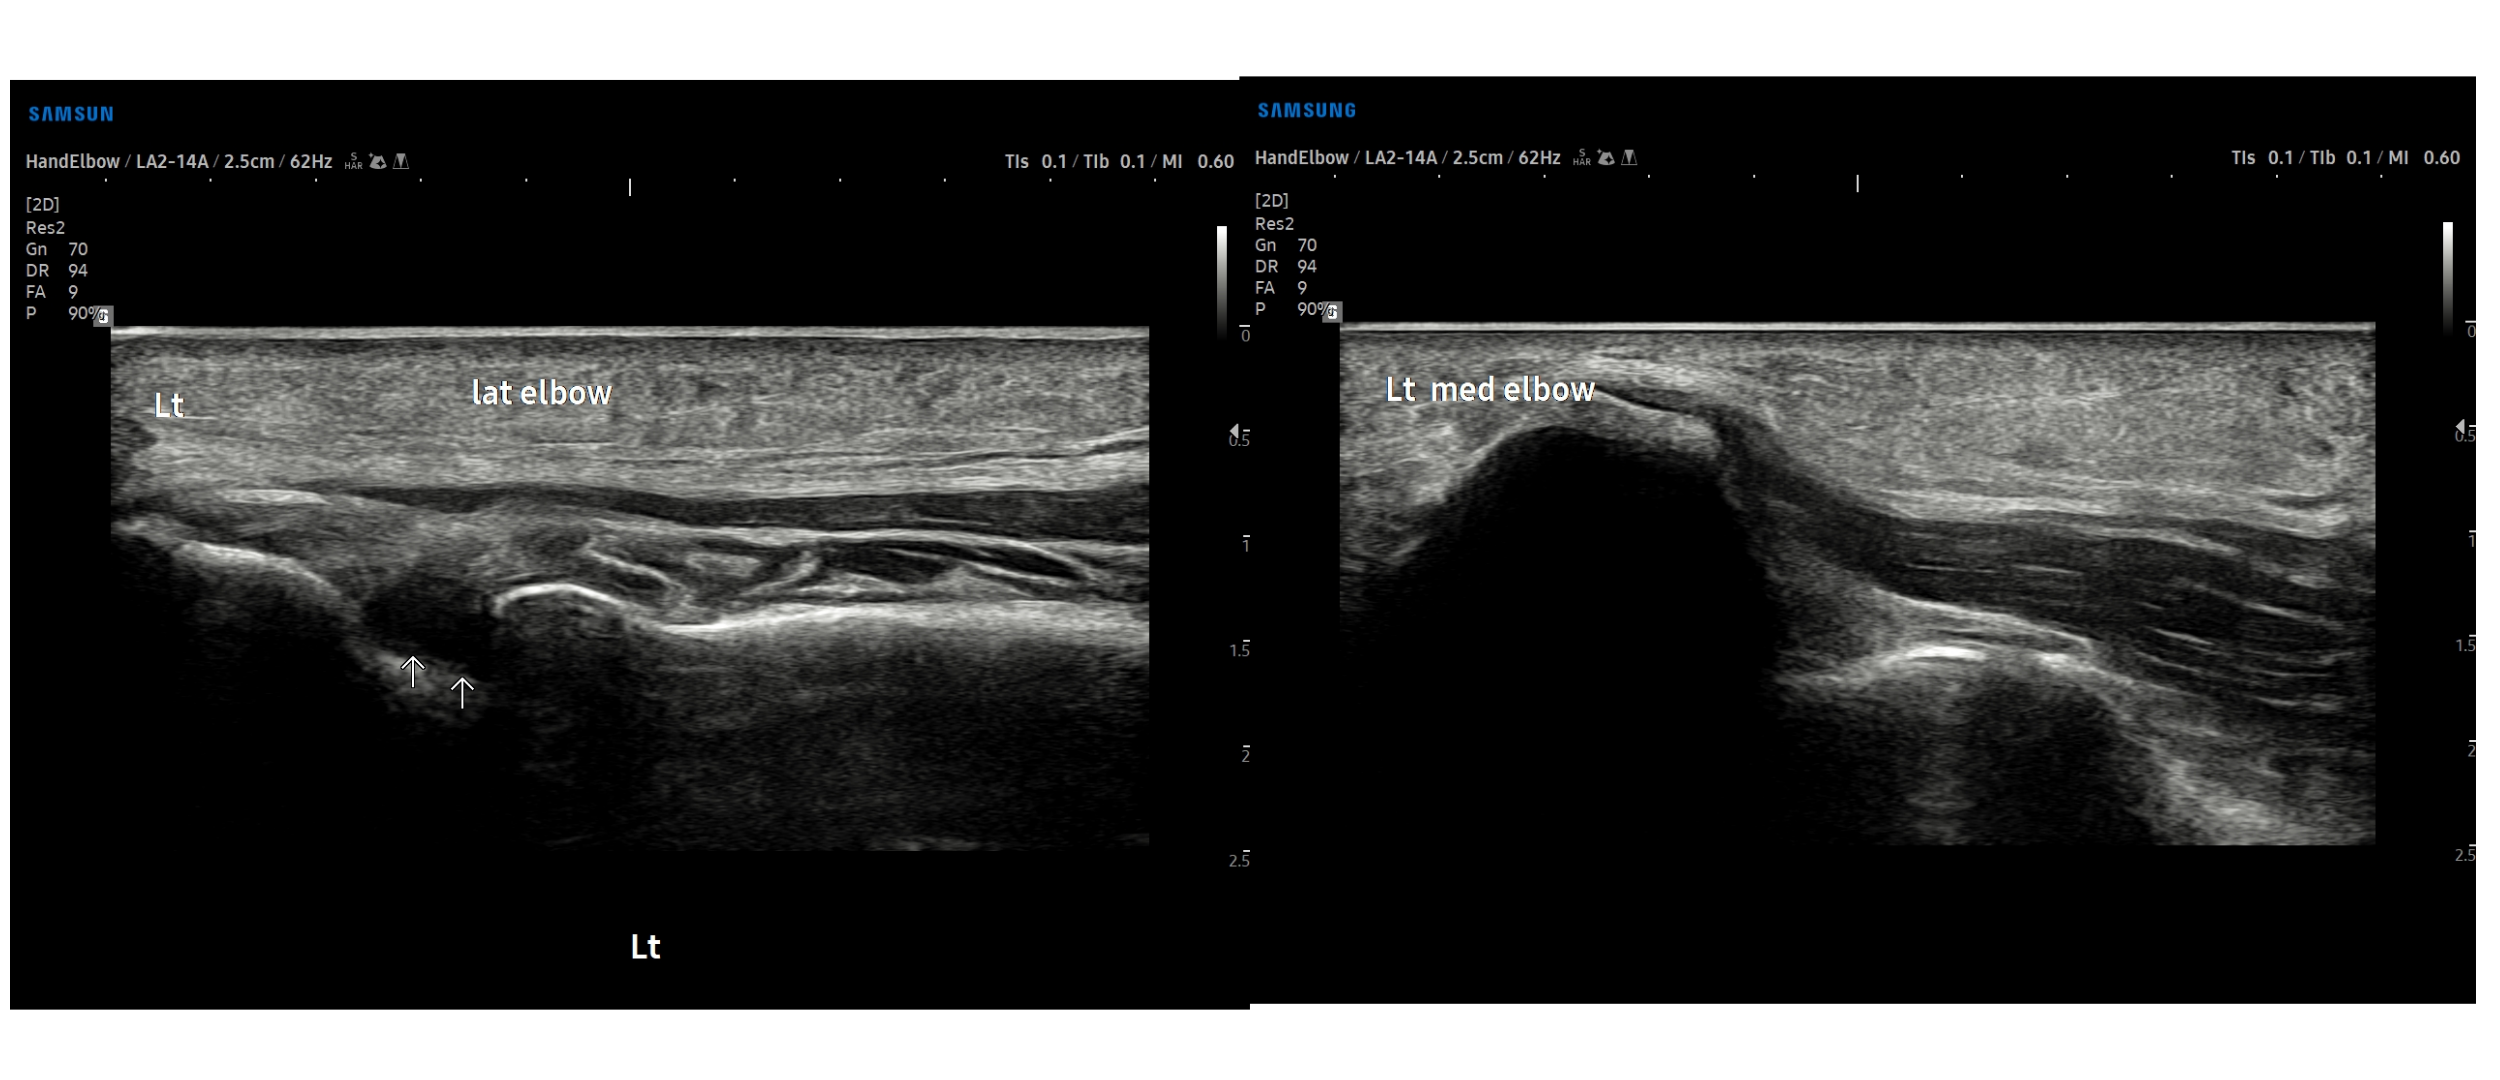

- 치료기간 : 25 . 8 .19 ~ 25 . 11 . 20

- 치료횟수 : 25 회 (사이클 치료 3 +아피톡신 10회)

치료 전

치료 후

좌측 골프엘보 : 12/2

좌측테니스엘보: 12/8

우측 골프엘보 : 12/2

우측 테니스엘보: 12/8